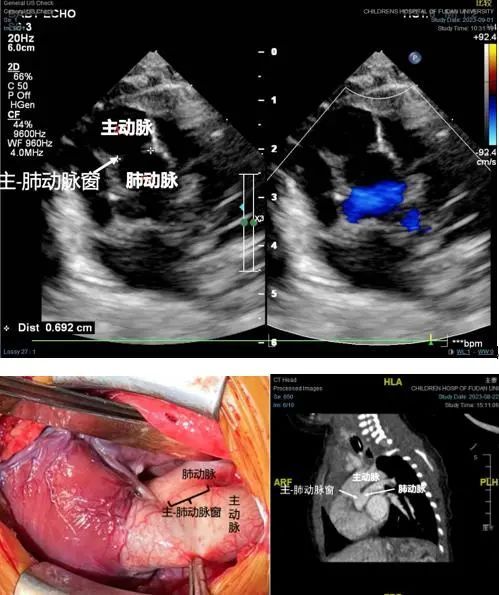

心外科叶明主任给出了答案:“因为他有一个很大的主-肺动脉窗,从心脏增强CT上来看,患儿的体循环和肺循环的血液通过主-肺动脉窗进行沟通混合,这是他能够存活下来并且症状不是非常严重的主要原因。”

“手术难度和风险极大,但这也是小亿存活的唯一机会。”叶明主任介绍,完全性大动脉转位合并主-肺动脉窗的病例在国内外鲜有报道,借鉴经验十分有限。针对这一罕见病例,为了最大程度确保安全,复旦儿科发挥国家儿童医学中心的学科优势,通过多学科会诊后确定手术方案、术后监护、术后ECMO(体外膜肺氧合)支持等治疗策略。经过充分沟通,小亿的家长同意手术方案。